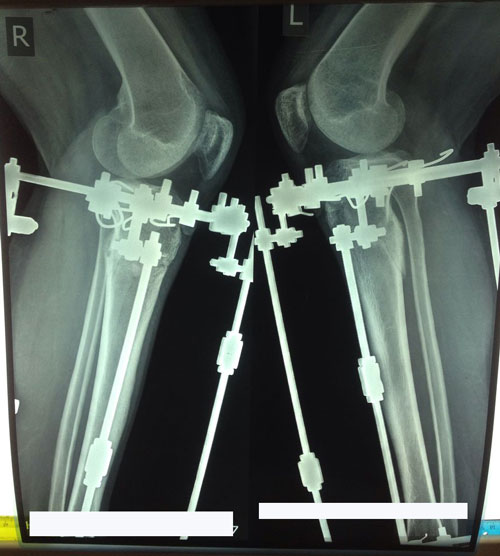

Рентген в 60 дней.

Процесс сращения идёт хорошо, ждём повторный рентген в 80 - 85 дней.

Дата операции 10.02.2017г.

Дата снятия аппаратов 10.05.2017г.

Срок лечения 90 дней.